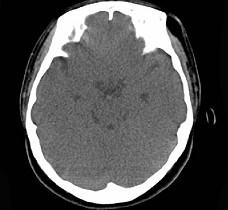

问题 女,31岁,在左眶外上缘发现一包块,质软,余所见无明显异常。如图所示病灶应诊断为 ( )

选项 A、表皮样囊肿 B、淋巴管瘤 C、错构瘤 D、脂肪瘤 E、畸胎瘤

答案 D